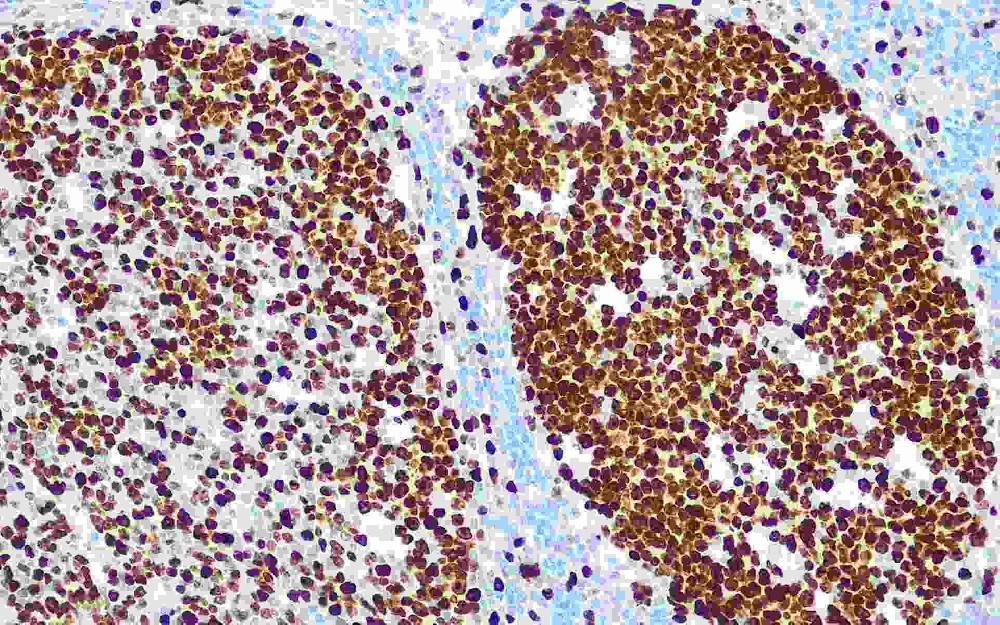

DNA錯配修復蛋白是一組核酶,在細胞增生期中DNA復制時參與錯配堿基的修復,這些蛋白與異常部位的DNA結(jié)合并將其移除。如果缺乏DNA錯配堿基修復酶,導致復制錯誤DNA的堆積在增生的細胞中不能被修復,這種現(xiàn)象稱為高頻度微衛(wèi)星不穩(wěn)定性,與之相對應(yīng)的是低頻度微衛(wèi)星不穩(wěn)定性和微衛(wèi)星穩(wěn)定。在人類DNA 錯配基因突變率高并與腫瘤相關(guān)的有MLH1(49%),MSH2(38%),MSH6(9%)和PMS2(2%)。DNA錯配修復蛋白缺陷和一些人類腫瘤有關(guān),比如遺傳性非息肉性結(jié)、直腸癌(HNPCC)。MLH1和MSH2突變者有超過70%發(fā)展為結(jié),直腸癌,50%發(fā)展為內(nèi)膜癌,但預(yù)后比低頻度微衛(wèi)星不穩(wěn)定性和微衛(wèi)星穩(wěn)定的患者好。與分子生物技術(shù)比較,免疫組織化學分析MMR簡單、便宜,多數(shù)實驗室可進行。所以,免疫組織化學檢測MLH1、MSH2、MSH6、PMS2被推薦為有家族遺傳性非息肉性結(jié)、直腸癌的人群的常規(guī)研究。